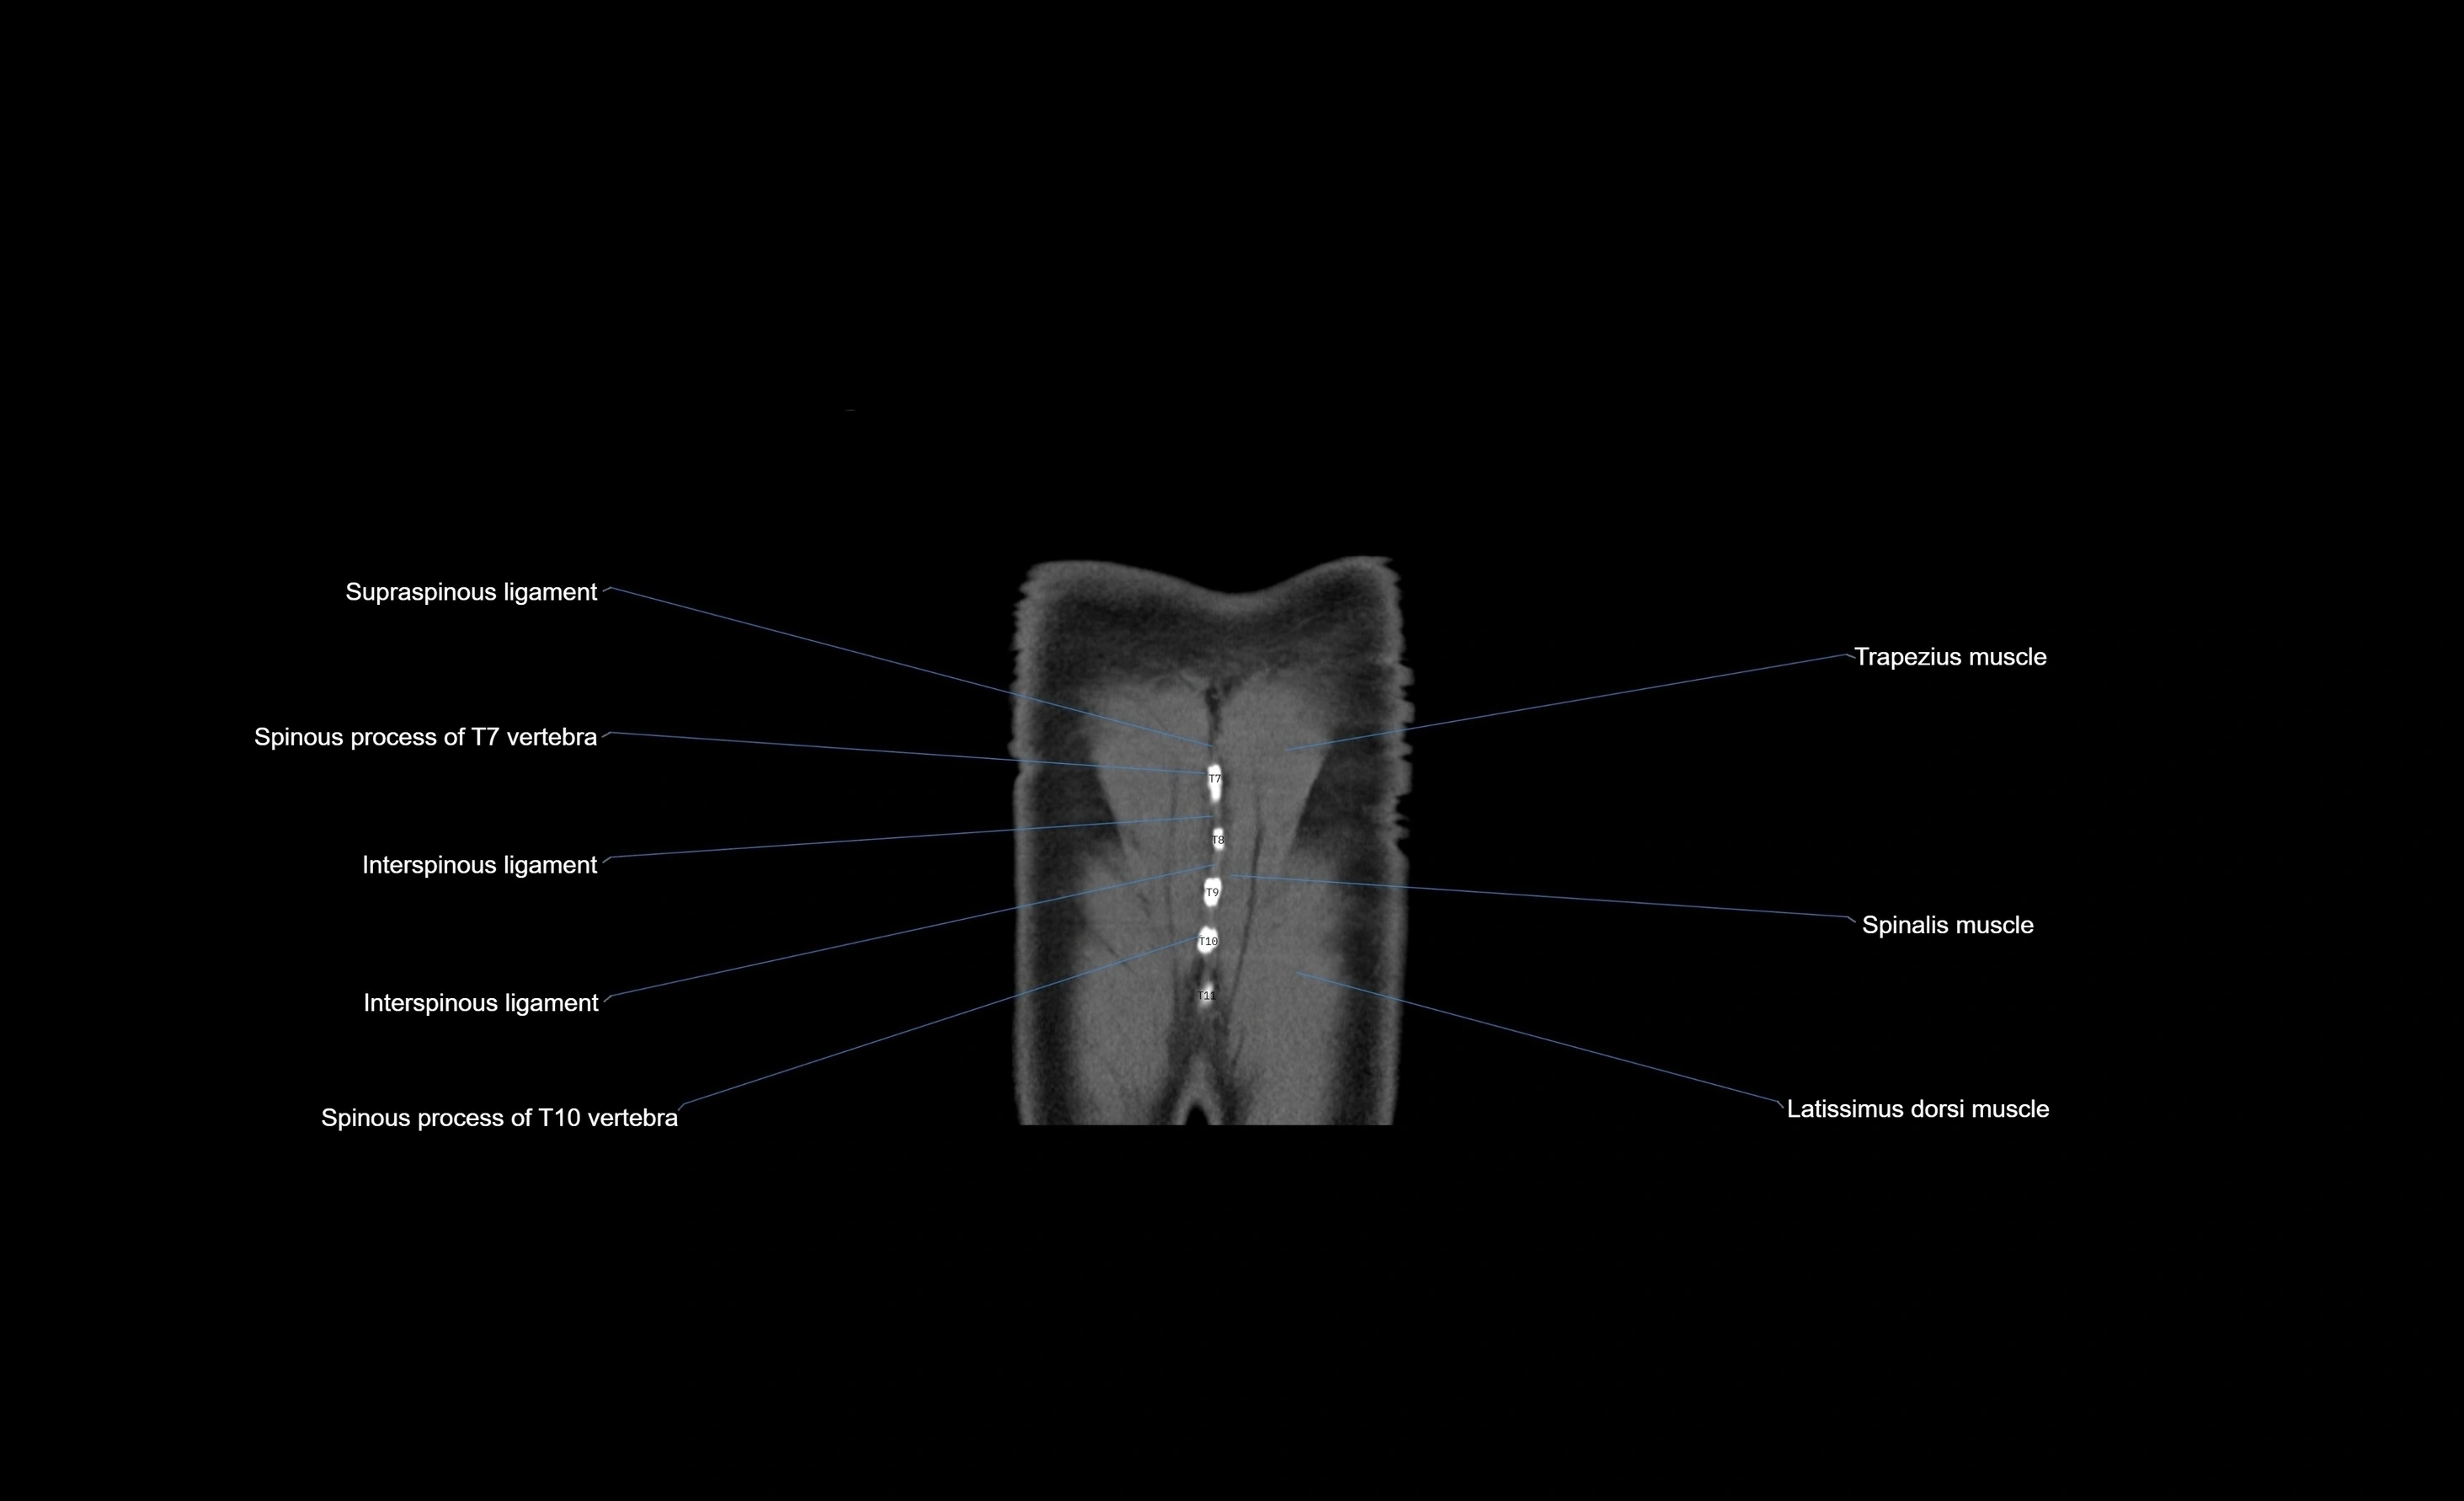

- Interspinous ligament

- Spinous process of vertebra

- Trapezius muscle

- Latissimus dorsi muscle

- Multifidus muscles